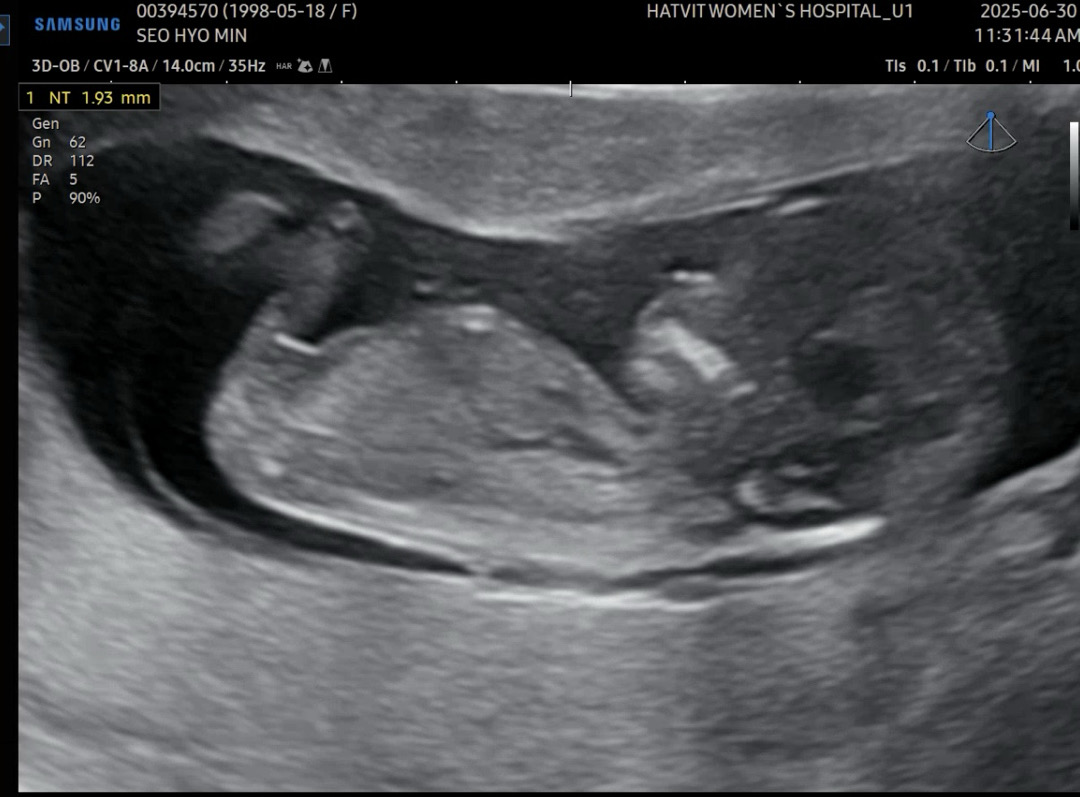

신랑은 공주님을 원한다시는데..ㅎ 오늘 본 뽀물이의 사진을 양가 부모님과.. 또한 베동에 올라온 각도법 보니 영락없이 아들같다시는데 베님들은 어떻게 보이시나요..? ㅎ